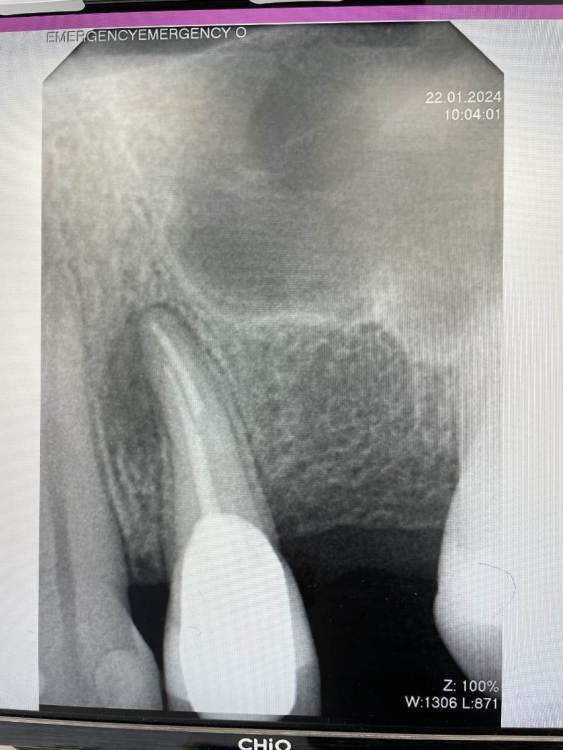

Ulitka Опубликовано 24 января, 2024 Поделиться Опубликовано 24 января, 2024 Добрый день. Уточните, пожалуйста, можно ли спасти зуб 24? Дня 4 назад появилась болезненность при надкусывании, сейчас боли нет ,но есть небольшая припухлость в области корня зуба. Один стоматолог сказал без 3Д снимка, что можно попробовать пролечить и заново протезировать. Второй по 3Д говорит, что у корня зуба нет частично кости, необходимо удалить зуб, чтобы прошло воспаление и кость восстановилась, далее имплантация. Прилагаю КТ https://drive.google.com/file/d/1xQxirzscf1404qjDOck7pBpt04szT7sa/view?usp=drive_link Ссылка на комментарий

wladdX Опубликовано 25 января, 2024 Поделиться Опубликовано 25 января, 2024 Пара скриншотов 1 Ссылка на комментарий